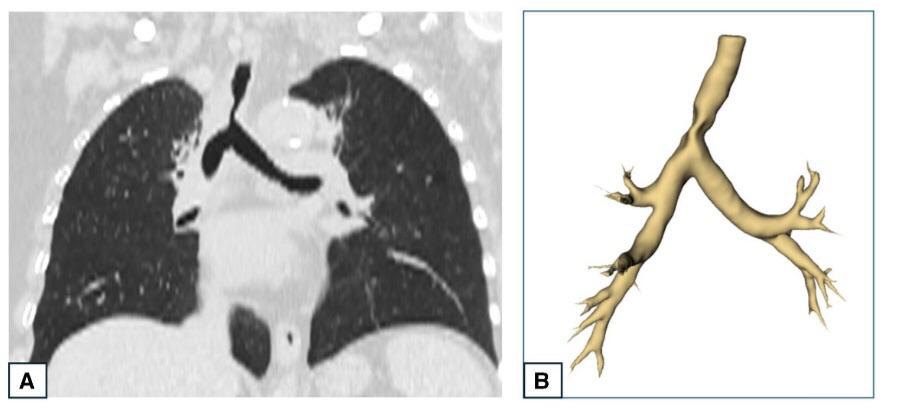

Il trattamento consiste nella ricanalizzazione della via aerea e nel posizionamento di protesi alfine di mantenere pervia la via aerea e preservare la ventilazione. La protesi deve essere conformata al paziente ed alla stenosi da trattare. Recentemente, la UOC di Chirurgia toracica ha pubblicato sulla rivista ufficiale della European Society of Thoracic Surgeons un lavoro sull’utilizzo della TAC tridimensionale alfine di valutare l’anatomia della stenosi delle vie aeree e scegliere la protesi da utilizzare. Tale studio permette di pianificare prima del trattamento la protesi che verrà poi posizionato nella via aerea. In caso la protesi non sia disponibile, la TAC tridimensionale offre la possibilità di fare produrre dalla ditta una protesi della forma e delle dimensioni adatte alla anatomia del paziente.